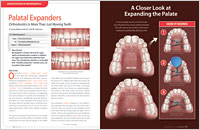

Crossbite is when one or more of the upper teeth bite inside the lower teeth rather than outside. This is usually related to misalignment of the upper and lower jaws. In a child who is still growing, widening the upper jaw with an orthodontic appliance called a palatal expander may solve the problem.

Crowding results from a lack of space for the teeth to fit normally within the jaws, either because the teeth are too big or the jaws are too small. Possible solutions may include removing some teeth and/or making more room in the jaws with a palatal expander or through a surgical procedure.

Palatal Expanders Orthodontics is more than just moving teeth. Orthodontists, with their advanced training in growth and development, have a variety of techniques and appliances besides braces at their disposal to correct bite problems. One of these is the palatal expander, which is used to create more room for an adolescent's permanent teeth. It does so by gently and gradually spreading apart the bones of the palate (roof of the mouth), which don't permanently fuse together until shortly after puberty... Read Article